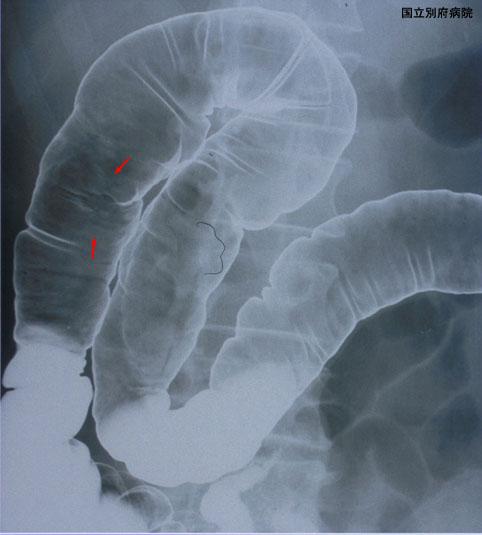

症例提示(所在地,施設名等): 大分県・ 別府医療センター

疾患(病理主体)の分類悪性上皮性腫瘍/腺癌

部位(臓器別)大腸/上行

検査方法X-P

腫瘍の肉眼分類0型(表在型)/IIc型(IIc+IIa)

病変の最大径(ミリ)15〜19

腫瘍の深達度sm